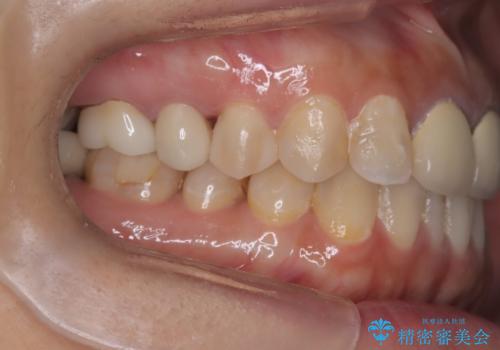

「右上4番目と5番目の間にフロスを通すといつも出血し、たまに臭いもする」という主訴で来院されました。

右上4番に歯冠色インレーが入っており、遠心側室エリアのマージン不適を認め、そこに汚れが溜まりやすい状態となっていました。

現在入っているインレー・CR裏層を除去し、再度CR裏層・セラミックインレー形成しました。